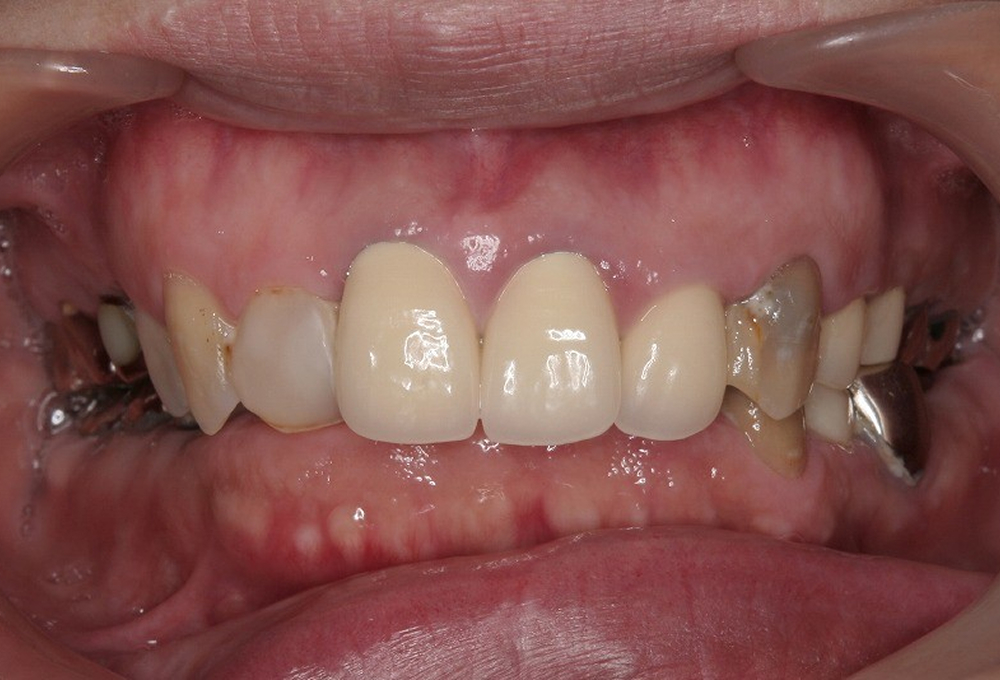

⑤矯正後補綴

⑥術後 ホワイトニング後セラミックにて修復